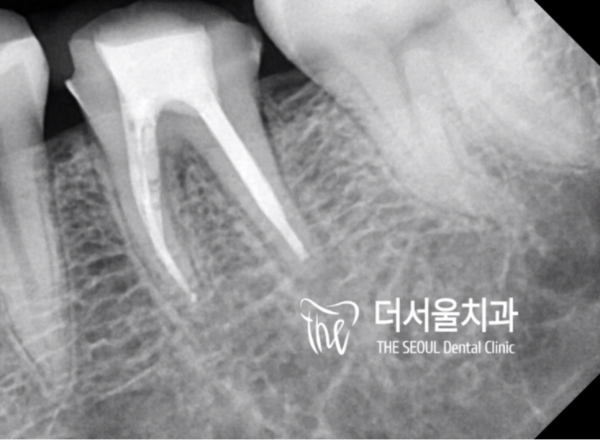

해당 치아를 신경치료하는 사진입니다.

감염이 되지 않도록 클램프와 러버댐을 이용하여

근관 내부를 청소, 소독하고 충전재료를 꼼꼼히 뿌리끝까지 채워넣습니다.

It's a picture of nerve treatment for the tooth.

Use a clamp and rubber dam to prevent infection

Clean and disinfect the inside of the root tube and carefully fill the filling material to the end of the root.

뿌리 끝까지 꼼꼼하게, 오염없이 충전재료를 잘 채워넣어야

또다른 문제가 생기지 않습니다.

치료후에도 문제가 생기지 않도록 해야하기 때문에

이부분을 아주 꼼꼼히 잘 치료합니다.

You have to fill up the roots thoroughly, without contamination

There will be no other problems.

We need to make sure that we don't have any problems after treatment

It treats this area very meticulously.